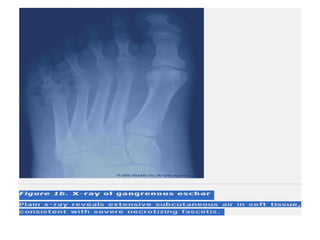

A benign-appearing dry gangrenous eschar

often hides an undrained infectious

collection